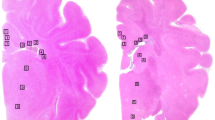

The hypothesis was tested that treatment with allopurinol, a xanthine oxidase inhibitor, or deferoxamine, a chelator of nonprotein-bound iron, preserved cerebral energy metabolism, attenuated development of edema, and improved histologic outcome in the newborn piglet at 24 h after hypoxia-ischemia. Thirty-two newborn piglets were subjected to 1 h of hypoxia-ischemia by occluding both carotid arteries and reducing the fraction of inspired oxygen; five newborn piglets served as sham-operated controls. The depth of hypoxia-ischemia was controlled by phosphorous magnetic resonance spectroscopy. Upon reperfusion and reoxygenation, piglets received vehicle (n = 12), allopurinol (30 mg/kg/d, n = 10), or deferoxamine (12.5 mg/kg/d, n = 10). The cerebral energy status was determined with phosphorous magnetic resonance spectroscopy. The presence of vasogenic edema was assessed by T2-weighted magnetic resonance imaging. Brain cell injury was assessed with caspase-3 activity, histology, and terminal deoxynucleotidyl transferase-mediated dUTP-biotin in situ nick end (TUNEL)-labeling. At 24 h after hypoxia-ischemia, the phosphocreatine/inorganic phosphate ratios were significantly decreased in vehicle-treated, but not in allopurinol- or deferoxamine-treated piglets. Water T2 values were significantly increased at 24 h after hypoxia-ischemia in cerebral cortex, thalamus, and striatum of vehicle-treated piglets, but not in allopurinol- and deferoxamine-treated piglets. No differences in caspase-3 activity, histologic outcome, or TUNEL-labeling were demonstrated between the three treatment groups. We suggest that allopurinol and deferoxamine may have an additional value in the treatment of perinatal hypoxia-ischemia with other neuroprotective agents or in combination with hypothermia.